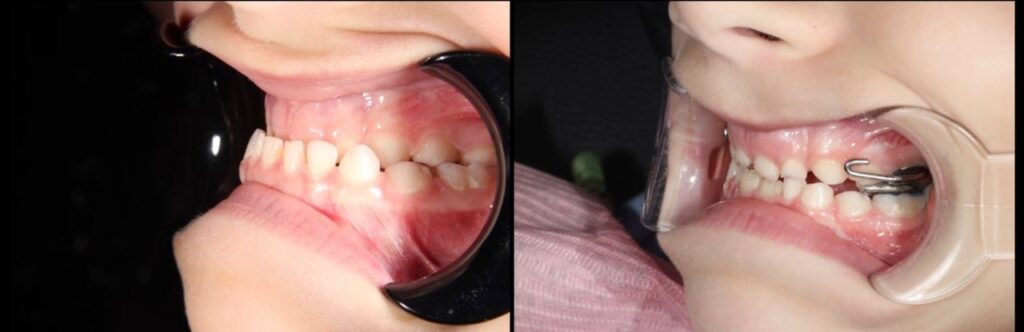

We proposed a two-stage solution based on modern approaches to growth correction:

- Marco Ross’s device — used to stimulate the growth of the upper jaw.

- The Dilar external oral appliance helps to correct the position of the upper jaw using external traction.

Why these devices? Because modern orthodontics does not inhibit growth but guides it in the right direction. And in the case of a 6-year-old child, this is the optimal age when it is possible to influence the development of the jaws with orthopaedic forces, without surgery.

- We installed the devices in one day. Immediately afterwards, we briefed the parents.

- Marco Ross’s device was activated within 21 days. After activation was complete, the screw was secured to prevent it from unscrewing due to bone pressure.

- A follow-up examination was conducted after 3 months. After another 3 months, the structure was removed.

- The total duration of treatment was 6 months.

The adaptation period lasted approximately 14 days. The boy quickly got used to the device. He was not even frightened by the external mask — on the contrary, he called it a “superhero device” and joked that it looked like a robot.